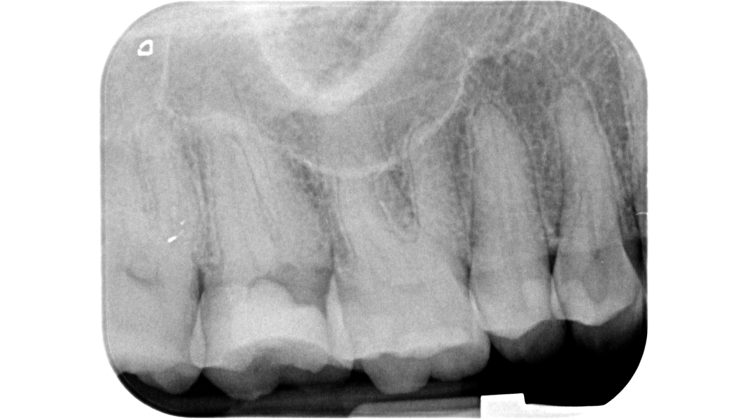

Una cavità d’accesso inadeguata per posizione, profondità ed estensione può determinare serie difficoltà nelle fasi successive, rendendo ad esempio difficile la localizzazione degli orifizi canalari, sottoponendo a eccessivo stress gli strumenti meccanici utilizzati o determinando un indebolimento della struttura dentale residua (Figure 1-5).

Devono essere valutate con molta attenzione la posizione dell’elemento in arcata e la sua inclinazione (Figure 6-7), l’entità e la posizione del processo carioso se presente, gli eventuali restauri posizionati sul dente e i rapporti con il parodonto: tutte queste considerazioni permetteranno al clinico di capire innanzitutto la mantenibilità e la possibilità di isolare mediante diga di gomma il dente. L’interpretazione degli esami radiografici consentirà inoltre di valutare alcuni parametri preoperatori di notevole importanza:

- presenza di radiotrasparenze periradicolari o periapicali;

- difetti ossei di origine parodontale;

- aspetto della camera pulpare e del sistema canalare;

- anatomia radicolare e canalare;

- presenza di pregresse terapie canalari e valutazione della qualità delle stesse;

- presenza o sospetto di riassorbimenti interni o esterni;

- presenza o sospetto di perforazioni e fratture.